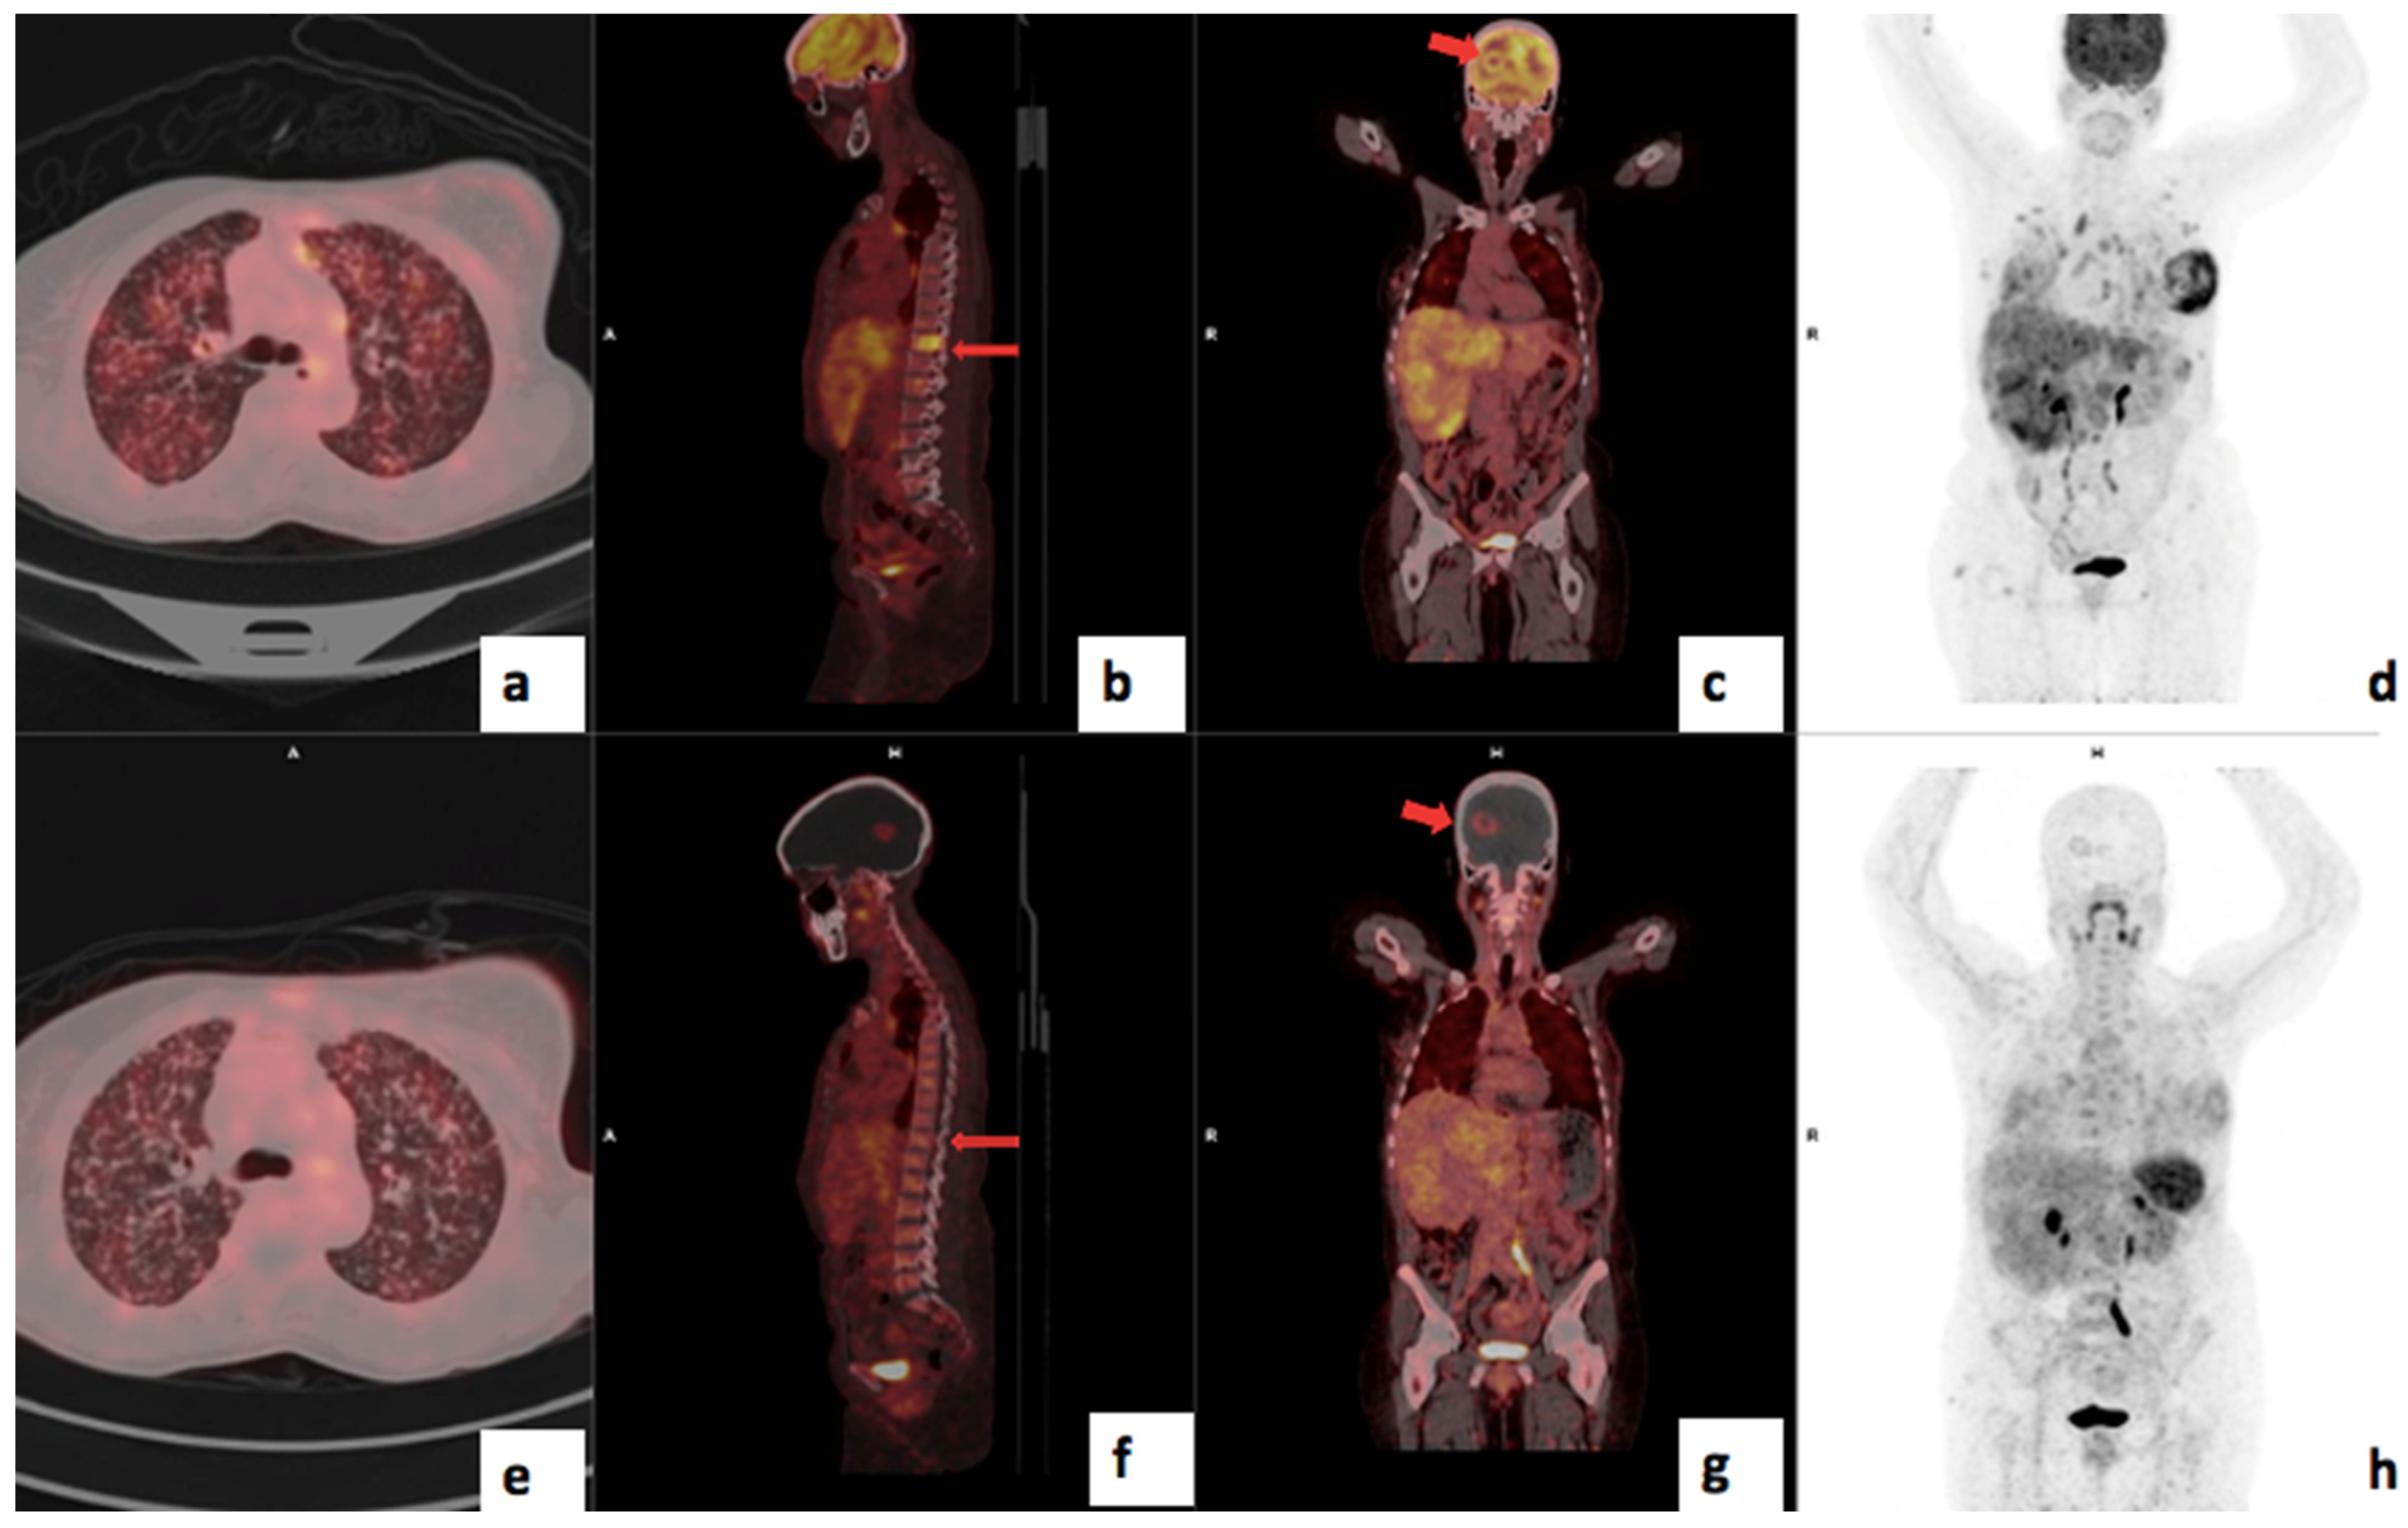

3.4. Visual Analysis

3.5. Treatment Response